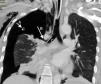

Paciente de 36 años que sufre un accidente de tráfico con colisión frontal de alta energía, que llega a sala de críticos en situación de insuficiencia respiratoria y signos de traumatismo torácico con datos indirectos de neumotórax. Se implanta de forma inmediata un tubo de drenaje pleural, sin mejoría clínica y sin reexpansión pulmonar en control radiológico. Se realiza tomografía computarizada (TC) torácica que evidencia la persistencia del neumotórax total derecho a pesar de una correcta posición del drenaje pleural (fig. 1A), con rotura bronquial (fig. 1B) a 2cm de la carina traqueal (fig. 1C). Para definir la localización y extensión de dicha rotura se realizó una reconstrucción mediante endoscopia virtual con TC helicoidal, en la que se aprecia la discontinuidad de la pared bronquial (fig. 2).